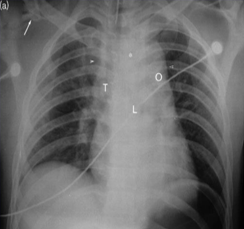

胸片 仰卧位 supine trauma patient ![]() 1. 上纵膈增宽 superior mediastinal outline widening 2. 支气管移位 tracheal deviation

3. 左侧支气管移位 displacement left bronchus

4. 主肺动脉窗消失 obliteration of aorto- pulmonary window.

5. 小肺尖帽 small apical cap.:肺尖帽为肺尖部的帽状病变,常由肺或胸膜纤维化向下牵拉胸膜外脂肪所致,也可能是慢性缺血导致的脏层胸膜透明斑形成的结果。其发生率随年龄增大而升高。也见于主动脉破裂所致血肿或其他位于壁层胸膜外或胸膜腔内的并发感染或肿瘤的积液者。

6. 肋骨骨折 rib fractures